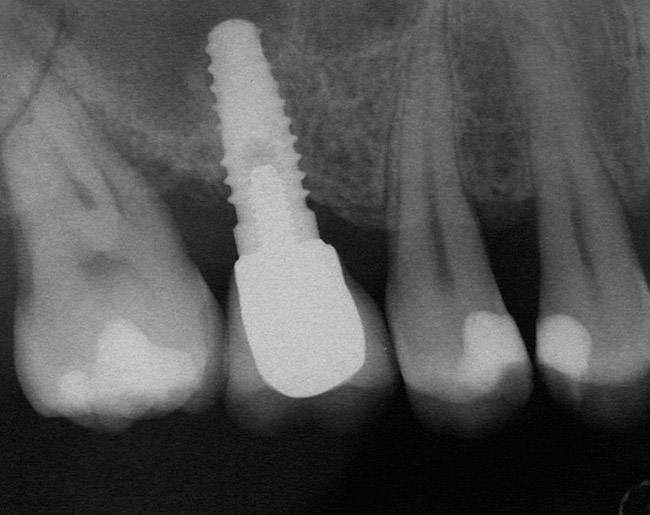

At the time of surgery, local infiltrative anesthesia was administered (lidocaine 2% with epinephrine, 1:100,000). A full-thickness mucoperiosteal flap was raised. The initial osteotomy was performed on midcrestal bone using a rose-headed bur. To prepare the osteotomy site for implant placement, sequential alternating osteotomes with variable conicity were used, drilling 2-mm shorter than the length of the implant to be placed (Figure 3A and Figure 3B). The implants presented initial primary stability (Figure 4), the cover screws were placed, and the implants were submerged for a healing period. The tissue was approximated, and the patient was instructed not to wear any denture or to place pressure on the healing site.

Figure 4  Implant positioning; the radiograph taken 4 weeks after placement confirmed good primary stability.

Figure 4